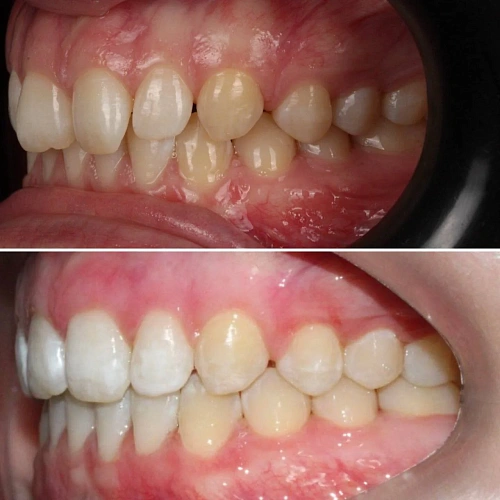

Скученность зубов, обе челюсти сужены — зубам не хватало места в ряду.

Брекет-система на обе челюсти. Расширить зубные дуги и убрать скученность. Срок — около 1,5 лет.

Проблема: Пациентка обратилась с одной жалобой — неровные зубы. При осмотре обнаружили, что обе челюсти сужены, зубам банально не хватает места, отсюда скученность. Зубы здоровые, ортопедия не нужна — чисто ортодонтический случай.

Решение: Установили брекеты на обе челюсти. Расширили дуги, убрали скученность — всё за 15 месяцев. Визиты раз в 4–6 недель для замены дуг. После снятия зафиксировали ретейнеры на обе челюсти, сняли сканы для кап. Ортопед подтвердил, что протезирование не требуется. Терапевт рекомендовал лечение — пациентка записана.

Скученность на обеих челюстях при сужении дуг — классический случай. Зубы здоровые, корни в хорошем состоянии, мотивация у пациентки высокая. Всё это позволило уложиться в 15 месяцев без осложнений. Ортопед подтвердил, что протезирование не нужно. Рекомендовала пройти терапевтическое лечение для полного завершени